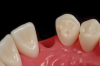

Next, the pontic must have resistance to facial displacement. This is accomplished by adding a slight extension on the pontic adjacent to an unbonded tooth; this will prevent the pontic from moving facially when loaded from the lingual (Figure 16). There should be no preparation on the unbonded tooth, nor should the extension be bonded so flossing may be easily accomplished. There must also be resistance form on the abutment, which can be best achieved with a vertical groove or box on the lateral surface of the abutment, adjacent to the edentulous site (Figure 17).29 There should be no excursive contacts on the pontic. Lastly, an evidence-based bonding protocol is essential for long-term success.

Fig 17. Ideal preparation with boxform retention on mesial of canine.